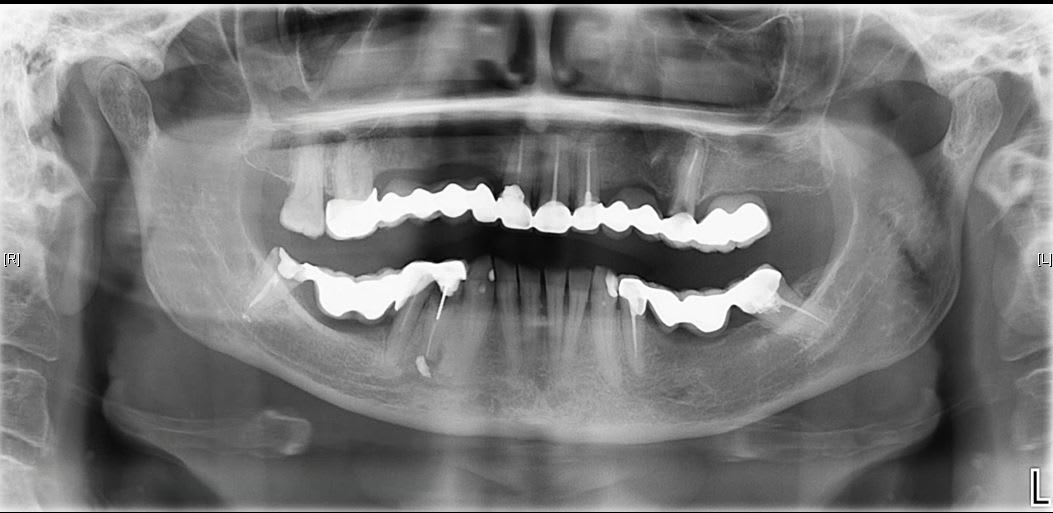

Osons ! Osons !

En place depuis 10 ans. Aucune mobilité.